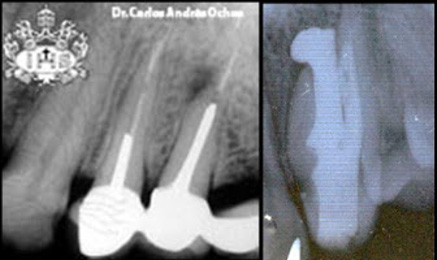

- Dientes que presentan tratamientos de conductos (Endodoncias)*

*Todo diente con tratamiento de conductos, puede tener FOCO incluso cuando aparezca íntegra en una radiografía.

Una endodoncia, o lo que comúnmente se conoce como “matar el nervio”, consiste, a grandes rasgos, en limpiar el tejido pulpar enfermo del diente y rellenarlo de nuevo con material biocompatible para posteriormente sellarlo. Éste es uno de [...]